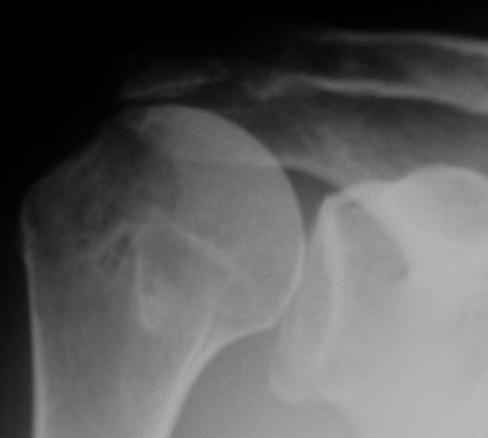

Верхний подвывих в такой ситуации может быть проявлением ротаторной артропатии, как следствия более массивного, чем частичный разрыв сухожилия надостной мыщцы, повреждения  вращательной манжеты. И значит нужно думать о том, насколько полно восстановлена манжета, адекватно ли был расценен объем ее повреждения. Что за шов применялся? Якорных винтов не видно. И почему гипсовая иммобилизация? Есть прекрасные надувные отводящие подушки, позволяющие ранние движения.

В качестве примера - снимки до и после восстановления целостности вращательной манжеты  после 3-хмесячной давности полного разрыва. Видно, что верхний подвывих устранен.